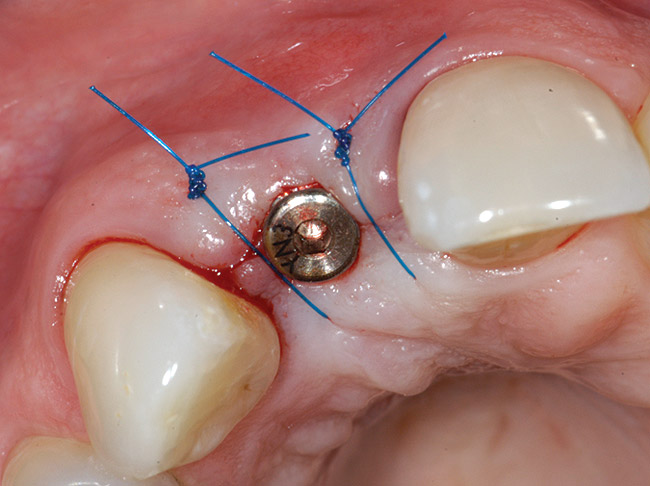

Treatment consisted of flapless extraction, socket grafting using mineralized bone allograft (Puros®, Zimmer Dental Inc, Carlsbad, CA), and a pedicled connective tissue graft36,37(Figure 11). Five months post-surgery, reentry was accomplished via a mid-crestal and labial sulcular incision. A crestal plasty was per- formed before implant placement into type II bone (Figure 12 and Figure 13). An immediate provisional was used for 3 months (Figure 14) before final crown fabrication (Figure 15).

Figure 12  Stage I surgery (implant shown with healing abutment), 4 months after extraction and socket graft.

Figure 12

Figure 13  Primary flap closure.